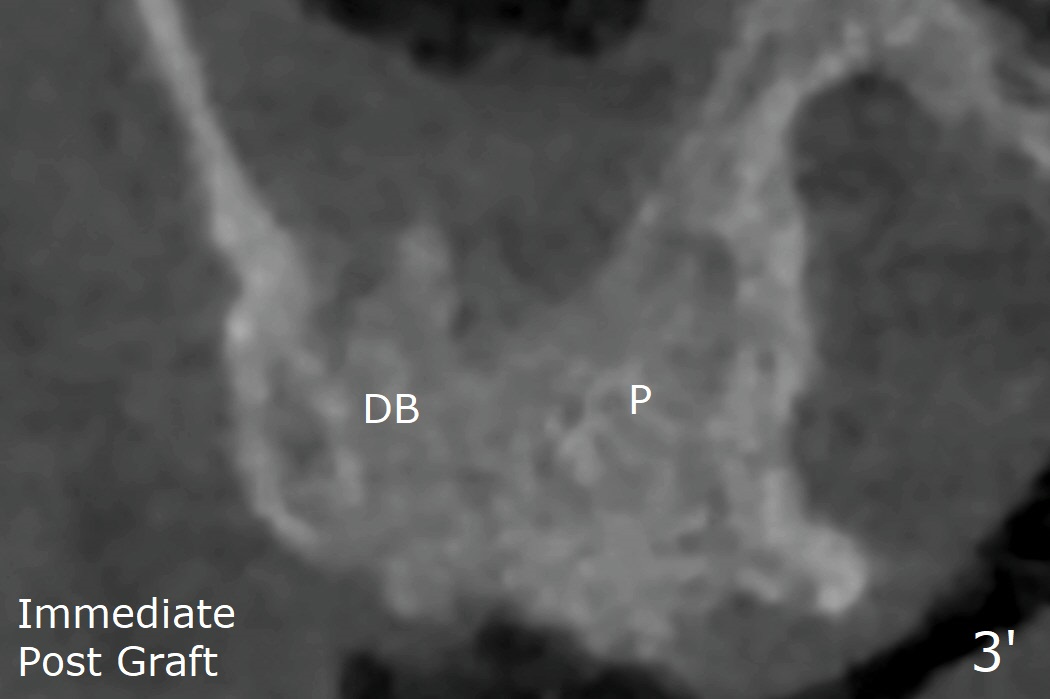

The dimension and density of the sockets will be measured 4-6 months later to determine whether rhPDGF-BB facilitates bone healing.